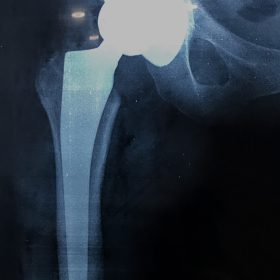

Παραδοσιακά οι αρθροπλαστικές ισχίου αποτελούνται από μια μεταλλική μπάλα – σφαίρα τοποθετημένη σε μια πλαστική κοιλότητα (κοτυλιαία πρόθεση).

Η πλαστική επιφάνεια στήριξης φθείρεται με την πάροδο του χρόνο, με ρυθμό μάλλον σχετιζόμενο με το επίπεδο δραστηριότητας του ατόμου. Αυτό έχει σαν επακόλουθο νεότεροι ασθενείς με μεγαλύτερο προσδόκιμο ζωής να έχουν αυξημένο ρίσκο αναγκαιότητας δεύτερης αρθροπλαστικής ισχίου (αναθεώρησης – Revision) επέμβαση που είναι πολυπλοκότερη και υπόκεινται σε υψηλότερο κίνδυνο επιπλοκών. Βάση των ανωτέρω, ιστορικά, η αρθροπλαστική ισχίου σπανίως εφαρμοζόταν σε ασθενείς κάτω των 60 ετών.

Χάρη στα νέα τεχνολογικά επιτεύγματα έχουν παραχθεί επιφάνειες στήριξης που ανταποκρίνονται σε μεγαλύτερα επίπεδα δραστηριότητας και αναμένεται να έχουν μεγαλύτερη διάρκεια ζωής. Αυτές οι καινούριες επιφάνειες στήριξης είναι συνήθως μέταλλο πάνω σε ειδικό σκληρότερο πλαστικό ή κεραμικό πάνω σε κεραμικό. Ως εκ τούτου, είναι τώρα πολύ πιο σύνηθες, νεότεροι ασθενείς να χειρουργούνται καθώς η πλειονότητα αυτών, που η αρθρίτιδα τους προκαλεί αφόρητους πόνους, επιλέγουν να έχουν ποιότητα ζωής από το να ζουν με τον πόνο.